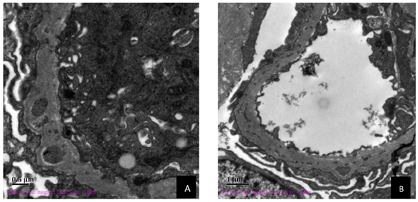

电镜描述:肾小球镜下可见2个肾小球,毛细血管内皮细胞明显空泡变性,个别管腔可见红细胞聚集,无明显内皮细胞增生,毛细血管袢开放。肾小囊壁层无明显增厚,壁层细胞空泡变性,无明显增生。基底膜不规则增厚,厚度达1300 nm。脏层上皮:上皮细胞肿胀,空泡变性,足突弥漫融合,基底膜内可见膜样结构。系膜区:系膜细胞和基质增生,未见电子致密物沉积。肾小管-间质:肾小管上皮细胞空泡变性,肾间质无特殊病变。肾间质血管:个别毛细血管管腔内可见红细胞聚集,小动脉未见病变(图1)。

病理诊断:足细胞内陷性肾小球病(PIG)。

患者,女性,36岁,因浮肿入院,表现为蛋白尿、血尿、高血压,入院后完善相关辅助检查提示外周血三系下降,抗核抗体阳性,补体下降,根据中华医学会风湿病学会提出的SLE诊断标准,符合"系统性红斑狼疮"诊断标准,但患者肾脏病理不支持"狼疮性肾炎"表现,另外,患者抗SSA抗体、抗SSB抗体阳性,但无口干、眼干、会阴干燥,且唇腺活检提示右下唇小块涎腺组织,腺泡组织周围少许淋巴细胞浸润,也不符合"干燥综合征",故临床考虑"未分化性结缔组织病"。结合患者肾脏损害轻,蛋白尿定量<1 g/24h,无血尿,肾功能正常。肾活检组织学病变轻,未见肾小球球性硬化及节段性硬化。肾小球系膜和基质轻度增生,毛细血管袢稍僵硬,基底膜增厚,钉突样结构不明显,肾小管间质轻度慢性病变。免疫荧光:免疫球蛋白IgM +,C3 ++,PLA2R染色阴性。肾脏病理电镜超微结构发现肾小球基底膜(GBM)增厚明显,内可见膜样和微管样结构。因此根据临床及病理诊断考虑足细胞内陷性肾小球病。

足细胞内陷性肾小球病(podocytic infolding glomerulopathy,PIG),是一类少见的特殊的肾小球形态学改变为特征,包括足细胞内陷及基底膜内微粒或微管结构。其病理机制尚未明确。日本报道较多。本例患者为中青年女性,肾炎综合征表现入院,外周血三系下降,抗核抗体阳性,补体下降,骨髓细胞学未见明显异常,根据中华医学会风湿病学会提出的SLE诊断标准,符合"系统性红斑狼疮"诊断标准,但患者肾脏病理不支持"狼疮性肾炎"表现,另外,患者无口干、眼干、会阴干燥,且唇腺活检也不符合"干燥综合征",故临床考虑"未分化性结缔组织病"。肾脏病理电镜超微结构发现肾小球基底膜(GBM)增厚明显,内可见膜样和微管样结构。因此病理诊断支持足细胞内陷性肾小球病(podocytic infolding glomerulopathy,PIG),这是国内继2015年8月徐峰等[1]首次报道后的第2例报道。